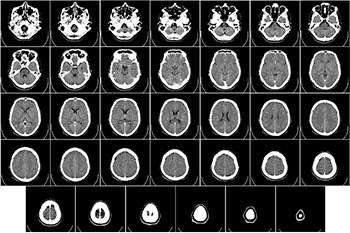

뇌출혈의 뇌 CT 영상

뇌출혈의 뇌 MRI 영상 뇌출혈은 뇌 CT, 뇌 MRI 검사로 부위와 출혈량 등을 확인할 수 있습니다.뇌출혈의 초기 증상으로 두통, 어지럼증(어지럼증), 오심(구역질), 구토가 나타나는데, 식체 증상과 유사하게 구별이 어려운 경우도 있고 심하면 의식 소실, 간질 발작을 동반합니다.